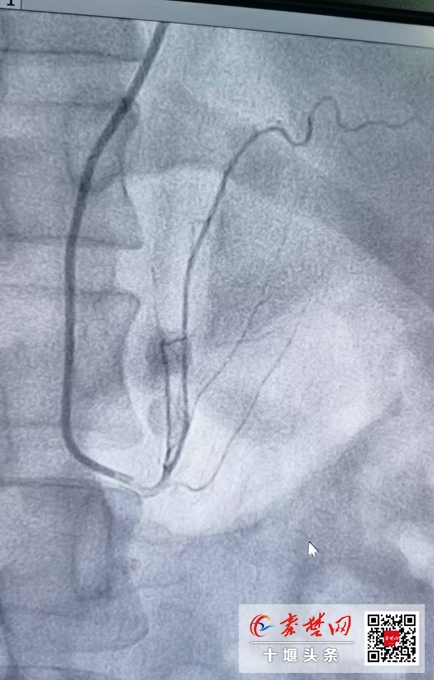

据赵继先主任介绍,经皮超选择性肾上腺动脉无水酒精栓塞术是国内治疗原发性醛固酮增多症的最新技术。该手术为微创手术,在患者全程清醒的状态下进行局部麻醉,经桡动脉上的一个小小针眼,精确找到病变所在的肾上腺动脉,然后用无水酒精消超选择性融掉肾上腺病变的位置,减少或阻断醛固酮的产生,降低血压,达到减少心脏、脑、肾脏的器官损害的目的。

手术历经30分钟,在心内一病区沈俊博士、范群雄副主任医师、夏南博士组成的介入团队紧密协作下,手术顺利完成。

赵继先介绍,原发性醛固酮增多症(primary aldosteronism,PA)是指肾上腺皮质分泌过多的醛固酮,临床上主要表现为高血压和低血钾。与原发性高血压患者相比,PA患者心脏、肾脏等高血压靶器官损害更为严重,因此早期诊断、早期治疗至关重要。而选择性肾上腺动脉栓塞术(SAAE)是一种微创手术,经导管动脉内将无水乙醇等栓塞剂选择性地注入到肾上腺病灶组织的供血动脉,使之发生闭塞,中断血供,让病变肾上腺坏死,从而到达抑制醛固酮过量分泌的目的。

近年来,SAAE成为原发性醛症患者的新选择,相较于外科手术花费更少、住院时间更短,同时也可以有效避免手术切除的大部分并发症,并且血管再通可能性少,是一种微创、快捷、经济且疗效确切的治愈PA的安全有效方法。但由于肾上腺动脉管径较细、开口起源变异性很大、术前难以精准定位腺瘤或增生组织的供应血管,因此,SAAE手术难度大,需要具备较高的介入技术,而全国开展此手术的医院也并不多。